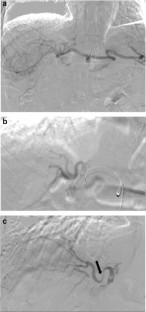

Fig. 1

Fig. 2